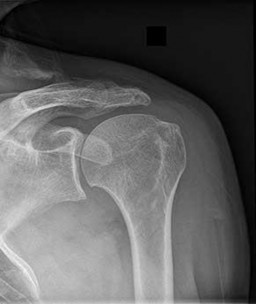

Question 10:

According to recent quantitative anatomical studies utilizing MRI and gadolinium, which of the following vessels provides the principal intraosseous blood supply to the humeral head, challenging historical teachings regarding proximal humerus vascularity?

Correct Answer: Posterior humeral circumflex artery

Explanation:

Historically, the anterior humeral circumflex artery (via its arcuate branch) was thought to be the primary blood supply to the humeral head. However, modern quantitative studies (e.g., Hettrich et al.) have demonstrated that the posterior humeral circumflex artery provides the vast majority (approximately 64%) of the intraosseous blood supply to the humeral head.